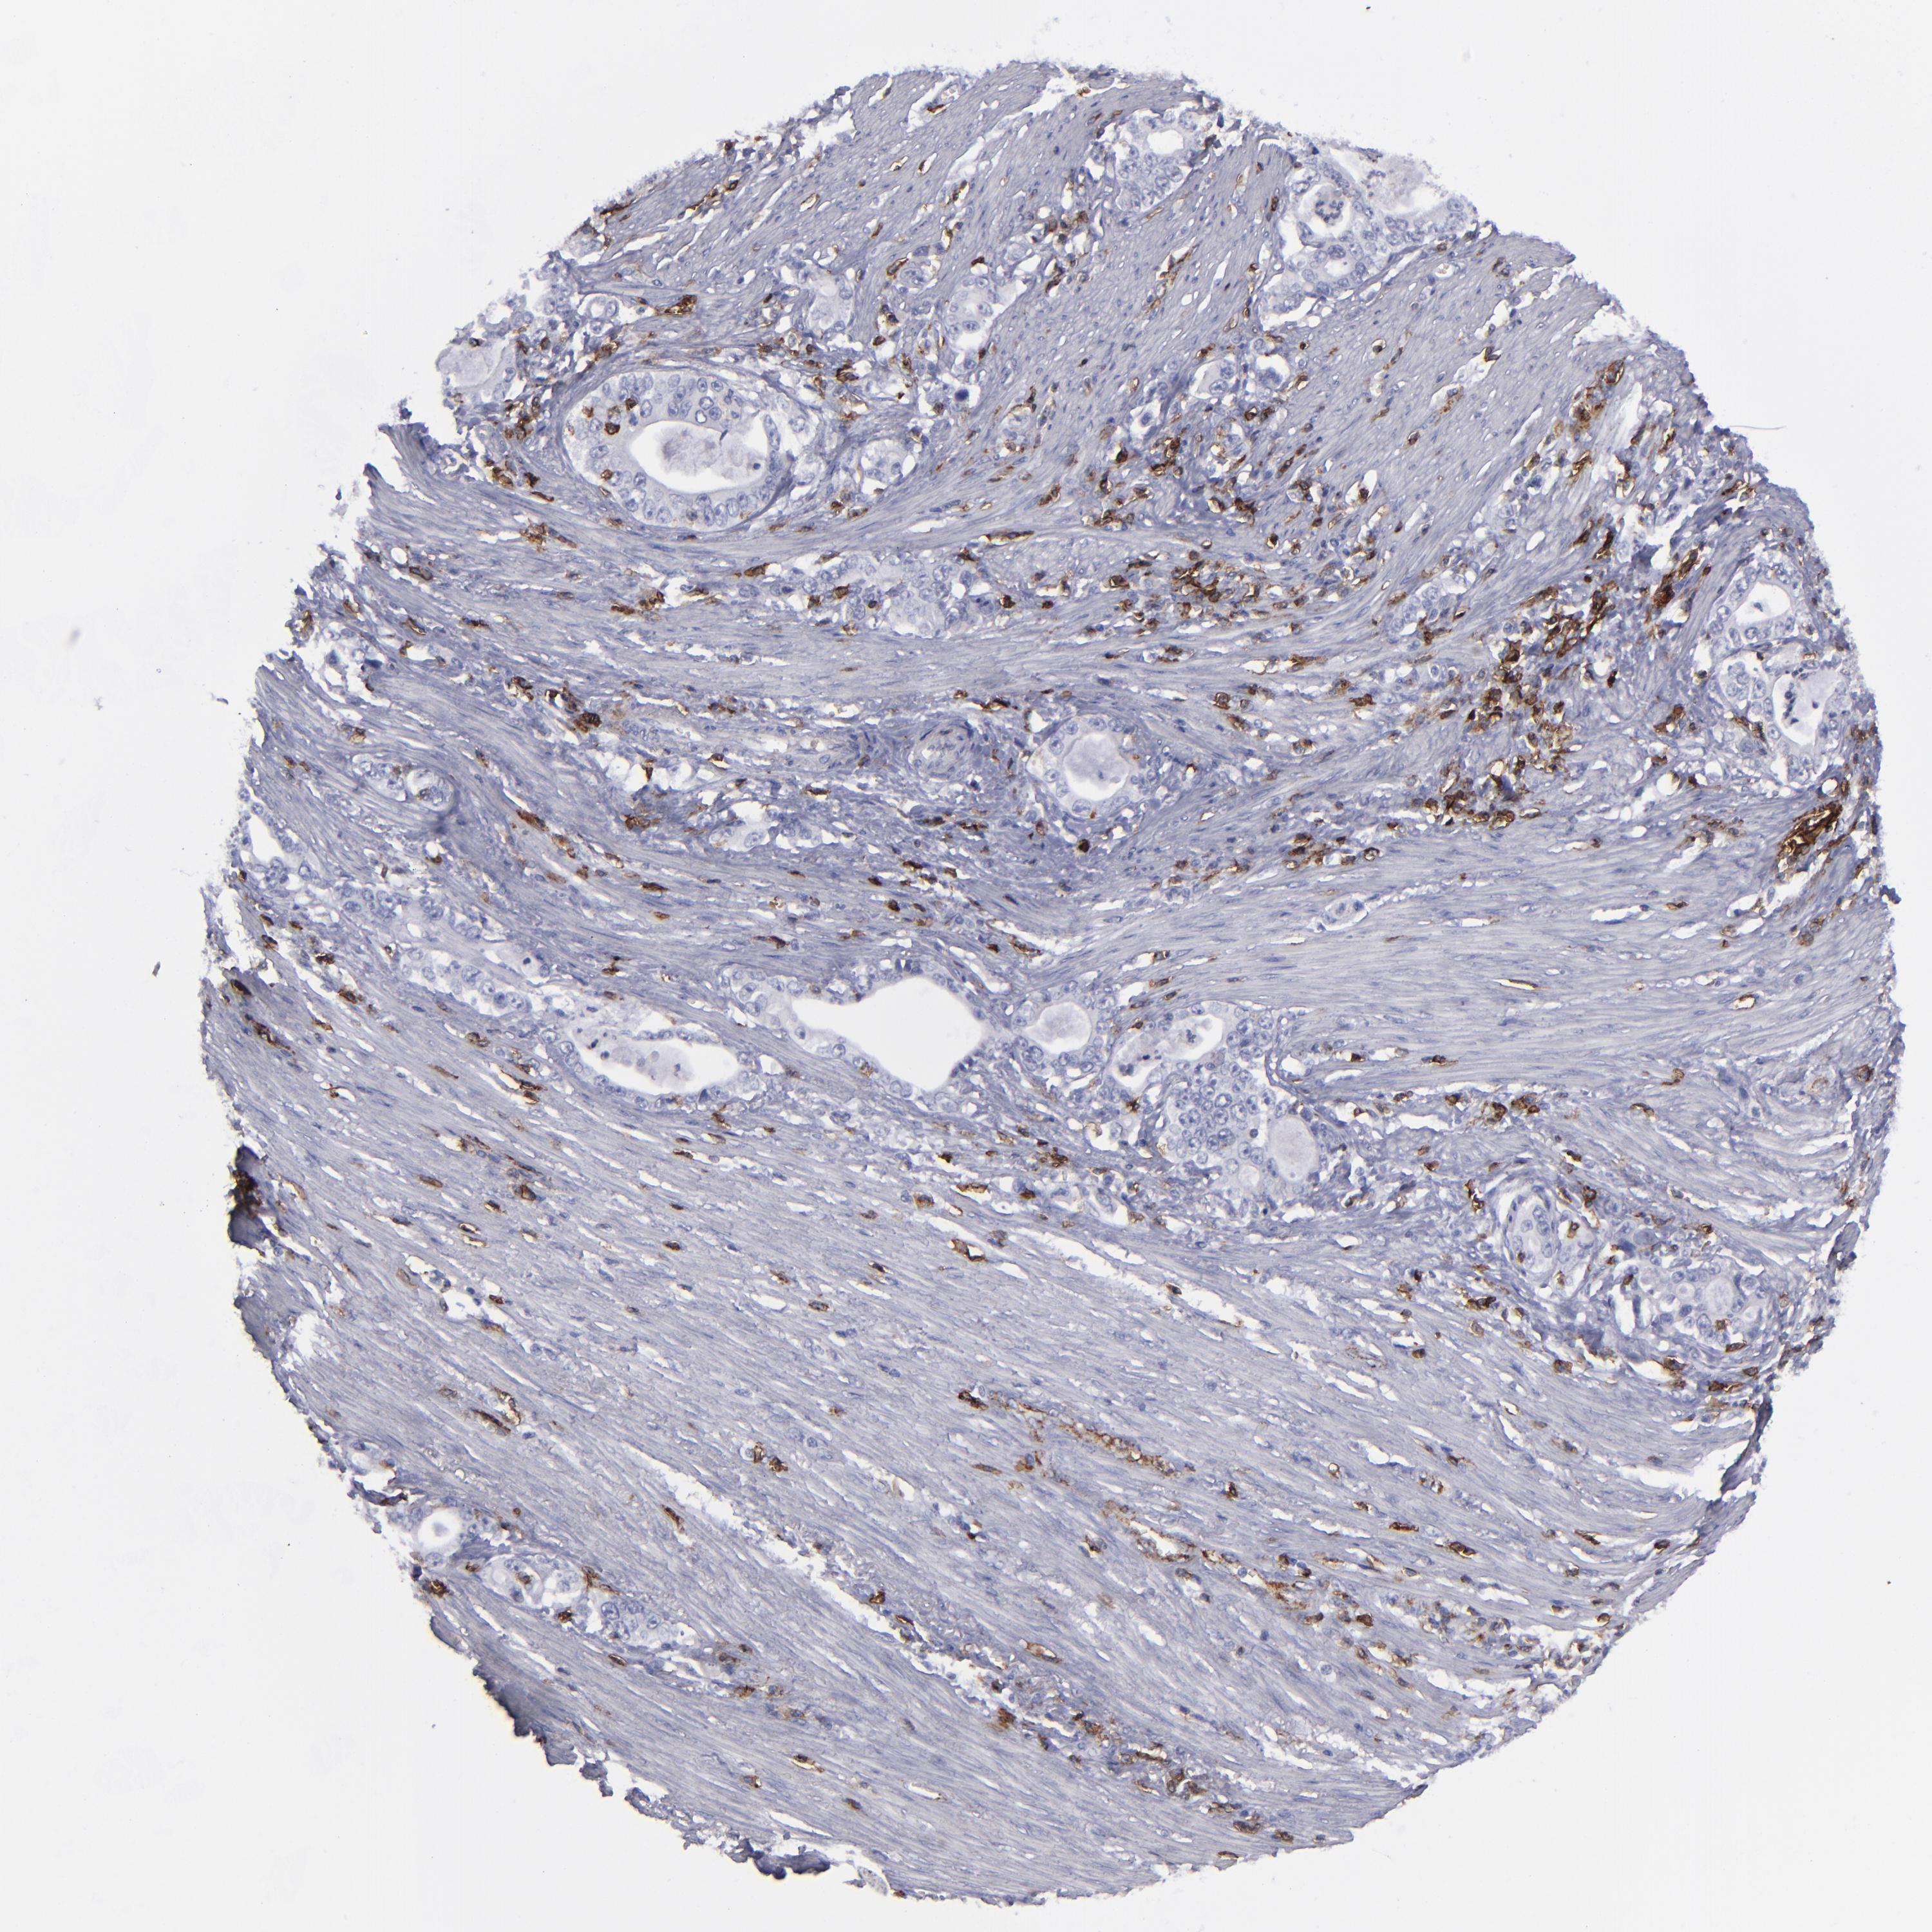

STOMACH CANCER - Protein expressioni

A mouse-over function shows sample information and annotation data. Click on an image to view it in a full screen mode. Samples can be filtered based on level of antibody staining by selecting one or several of the following categories: high, medium, low and not detected. The assay and annotation is described here.

Note that samples used for immunohistochemistry by the Human Protein Atlas do not correspond to samples in the TCGA dataset.

Antibody stainingi

Antibody staining in the annotated cell types in the current human tissue is reported as not detected, low, medium, or high, based on conventional immunohistochemistry profiling in selected tissues. This score is based on the combination of the staining intensity and fraction of stained cells.

Each image is clickable and will lead to virtual microscopy that enables deeper exploration of all samples and also displays staining intensity scores, fraction scores and subcellular localization as well as patient and tissue information for each sample.

Antibody HPA038936

Antibody CAB002420

Antibody CAB080304

Staining

High

Medium

Low

Not detected

Intensity

Strong

Moderate

Weak

Negative

Quantity

>75%

75%-25%

<25%

None

Location

Nuclear

Cytoplasmic/membranous

Cytoplasmic/membranous,nuclear

Adenocarcinoma, NOS

Adenocarcinoma, High grade